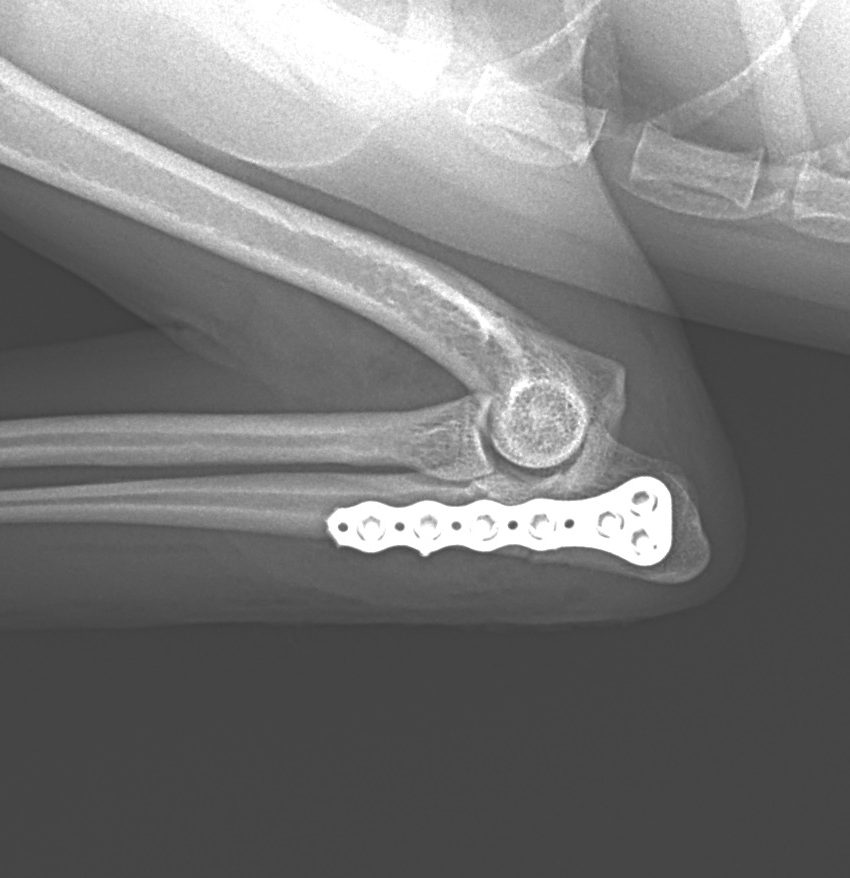

尺骨近位端肘頭骨折

尺骨の近位端の肘頭骨折をしているワンコがいるので手術で対応して欲しいと連絡がありました。高いところからジャンプして着地に失敗してしまったとの事です。さて、この部分の骨折は上腕三頭筋の牽引力に抵抗するための強固な固定が必要です。橈骨遠位端用の1.5 mm Titanium T-typeLocking Plateで接合術を行います。手術をする事で、早々に肘の曲げ伸ばし運動などのリハビリテーションを実施する事が可能となり、後遺症の発生を少なくする事を目的としています。